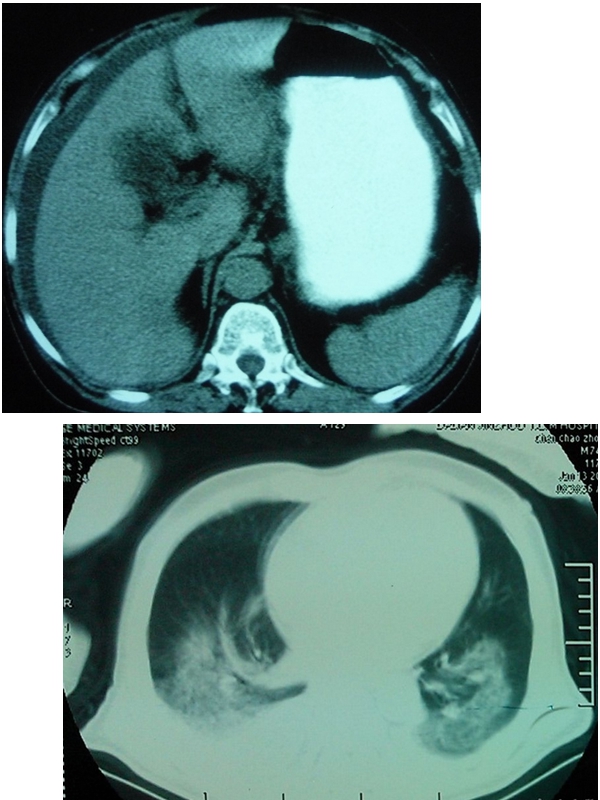

胸水腹水鑑別ct